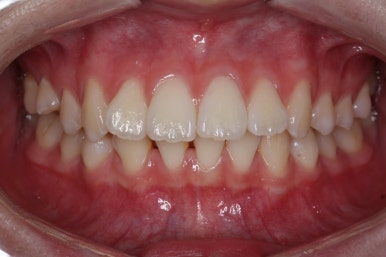

점점 단계가 진행될수록 얼굴의 중앙~윗니의 중앙~아랫니의 중앙이 점점 맞아가고 있음을 알 수 있습니다.

위아래 중앙도 어느 정도 맞아가고 있고, 발치를 한 자리와 결손치아 부위의 틈도 거의 없어져 가고 있습니다.

부산교정 키다리아저씨치과에서는 이번 환자분은 아래 앞니를 3개로 마무리하는 것이 아니라 송곳니를 끌어 당겨와서 앞니처럼 마치 앞니가 4개 있는 것처럼 마무리를 할 계획이어씨 때문에 정면에서 바라보았을 때 앞니 하나가 없는 느낌이 없이 어느 정도 중앙을 맞출 계회이였고, 원할히 진행되고 있음을 알 수 있습니다.

큰 그림은 거의 다 완성되었고, 디테일한 마무리 과정을 거친 후 치료를 종료하게 됩니다.